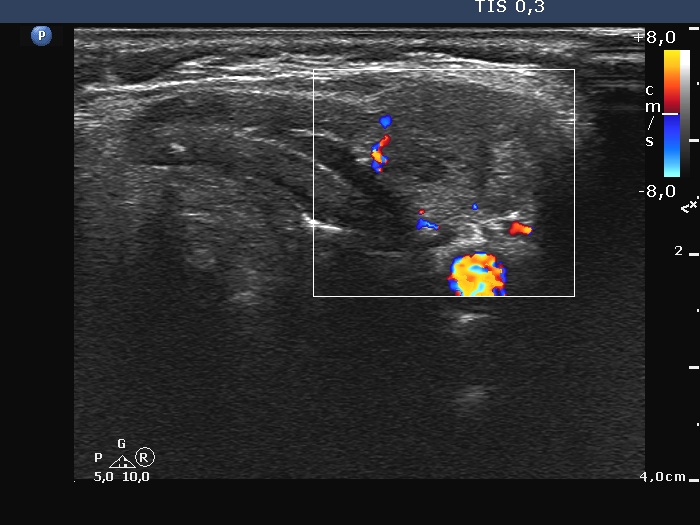

Left side of the neck, 7 cm above the thyroid, transverse scan, color Doppler mode. The sesion shows vascularity.